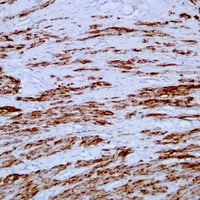

(Immunohistochemical analysis of Desmin staining in human liomyoma formalin fixed paraffin embedded tissue section. The section was pre-treated using heat mediated antigen retrieval with sodium citrate buffer (pH 6.0). The section was then incubated with the antibody at room temperature and detected using an HRP conjugated compact polymer system. DAB was used as the chromogen. The section was then counterstained with haematoxylin and mounted with DPX.)